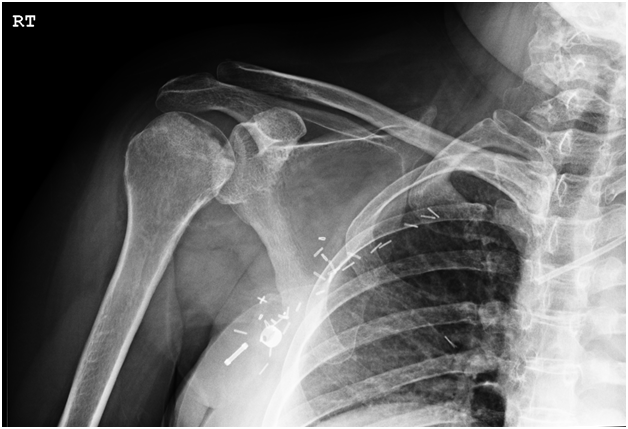

Radiographs revealed osteonecrosis of both humeral heads (Figure 1 & 2) with subchondral collapse bilaterally and mild arthrosis of the left glenohumeral joint. She had seen several orthopaedic surgeons regarding her severely disabling shoulder pain. It was determined that due to progressive CNS metastatic disease and recent hospitalization for gastrointestinal bleeding requiring transfusion that this patient was at unacceptably high risk for an arthroplasty procedure. Non operative therapy, including multiple opiate based pain medications, had failed to improve her quality of life so a less risky treatment was sought.

Figure 1 AP radiograph of the right shoulder. There is sclerosis of the humeral head as well as subchondral collapse present. There is osteophyte formation at the inferior humeral articular surface as well as the inferior glenoid.